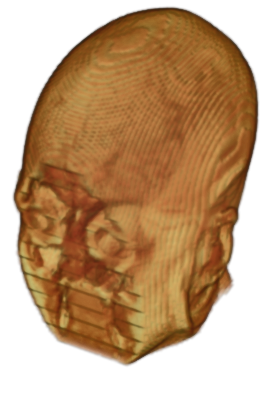

The digitalization of heath records has increased the risk of –and impact of– large scale data leaks. Although data compliance standards have been enacted to protect health records (HIPAA and GDPR), privacy of medical data is a growing concern. Three-dimensional scans such as magnetic resonance images (MRI) and computed tomography (CT), for example, contain an intrinsic privacy risk [Lotan et al.(2020)Lotan, Tschider, Sodickson, Caplan, Bruno, Zhang, and Lui]. Detailed renderings of the head can be crafted from 3D scans using techniques such as volumetric raycasting, as in Figure 1. This vulnerability can expose the patient’s identity if the renderings are matched to a face database [Mazura et al.(2012)Mazura, Juluru, Chen, Morgan, John, and Siegel, Lotan et al.(2020)Lotan, Tschider, Sodickson, Caplan, Bruno, Zhang, and Lui].

![]() |

Therefore, in this work, we define a new class of de-identification techniques that remodels the privacy-sensitive regions without altering the content of medically relevant data (see Figure 1). Under such a remodeling approach, the face, eyes, oral and nasal cavities, etc. should exhibit realistic appearance and structure of appropriate size, but should otherwise be independent of the original data. To solve this task, we propose a novel model called Convex Privacy GAN, or CP-GAN, that conditions on a convex hull of the skull extracted from the scan to be de-identified. The generator learns to synthesize volumes that preserve medically-sensitive regions such as the brain, while non-invertibly remodeling privacy-sensitive characteristics from the original scan.